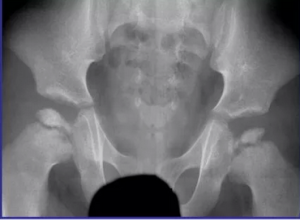

Наиболее значительные изменения, отражающие дефект энхондрального формирования костей у пациентов с RPL13-СЭМД, отмечены со стороны эпифиза головки бедренной кости. Типичный для RPL13-СЭМД паттерн характеризовался уменьшением размера ядра оссификации, снижением его высоты, фрагментацией и деформацией. Изменения в большинстве случаев носили двусторонний характер. У всех пациентов, у которых имелась возможность анализа динамики рентгенологических параметров, отмечено прогрессирующее течение большинства изменений (как рентгенометрических, так и качественных). Типичные изменения со стороны тазобедренных суставов у пациентов с RPL13-СЭМД представлены на рисунке.

Рисунок. Типичные изменения на рентгенограммах тазобедренных суставов у пациентов с спондилоэпиметафизарной дисплазией, ассоциированной с патогенными вариантами в гене RPL13: a) передне-задняя рентгенограмма тазобедренных суставов пациента (5 лет): уменьшение шеечно-диафизарного угла (черные линии), увеличение ацетабулярного индекса (белые линии), микроэпифиз справа (белая стрелка), фрагментация эпифиза слева (красная стрелка); b) передне-задняя рентгенограмма тазобедренных суставов пациента (7 лет): микроэпифиз справа (черная стрелка), фрагментация эпифиза слева (красная стрелка), неравномерная оссификация дна вертлужной впадины (белая стрелка), короткая шейка бедра (желтая стрелка); c) передне-задняя рентгенограмма тазобедренных суставов пациента (9 лет): фрагментация эпифиза справа (белая стрелка), снижение высоты эпифиза слева (красная стрелка), короткая шейка бедра (черная стрелка), экструзионный подвывих за счет латеральной миграции (желтая стрелка), шеечно-диафизарного углол нормальный (черные линии)